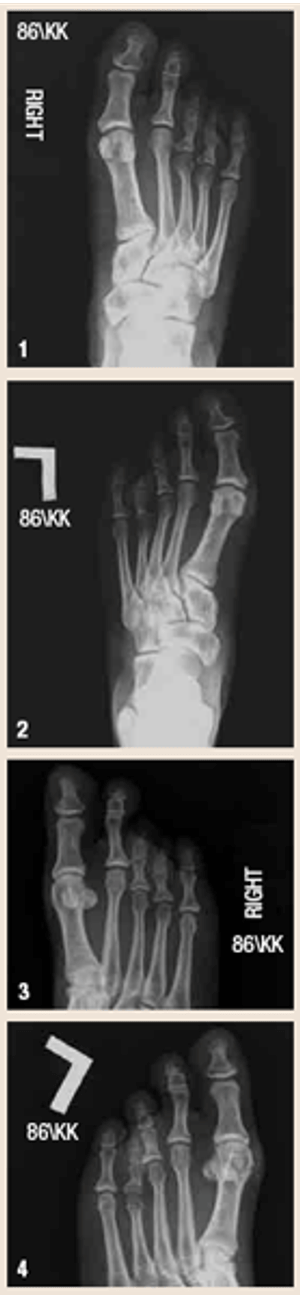

Bilateral brachymetapodyByAndrew Allmendinger, DO,Paul Yeghiayan, MD,Robert Perone, MDJune 27th 2011This 41-year-old woman presented with a known history of bilateral foot deformities and new complaints of bilateral foot pain. She had associated hallux valgus deformities.